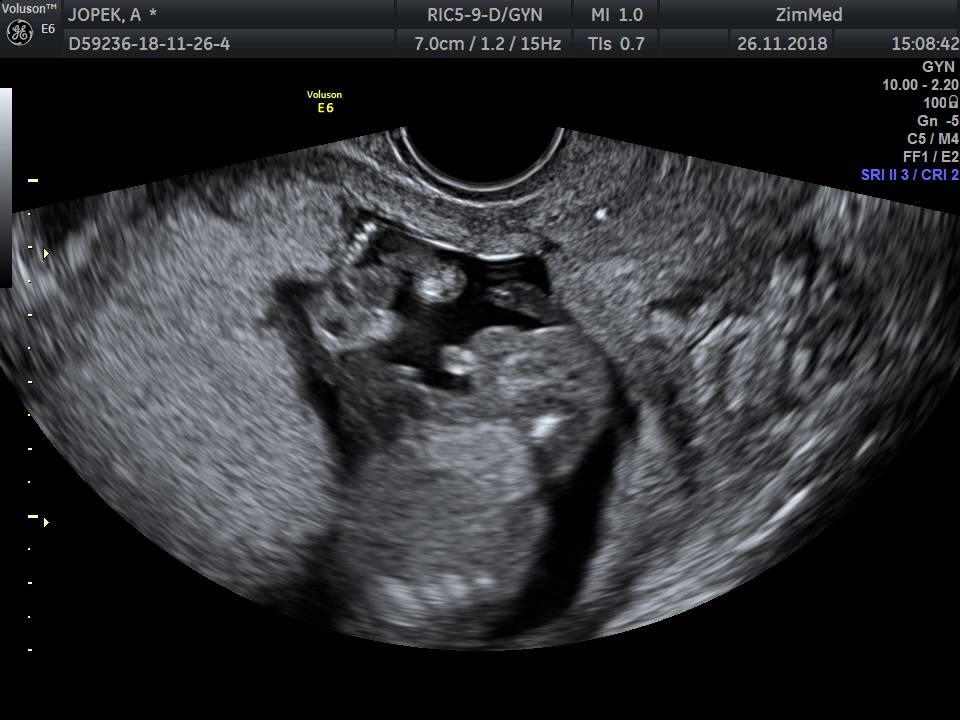

Nie mam nuba bo to juz 16tc wiec juz widac wszystko. Odstaje jak byk miedzy nogami jajka

IMG_20181126_1_5.jpeg

• IMG_20181126_1_5.jpeg

71,7 KB · Wyświetleń: 529